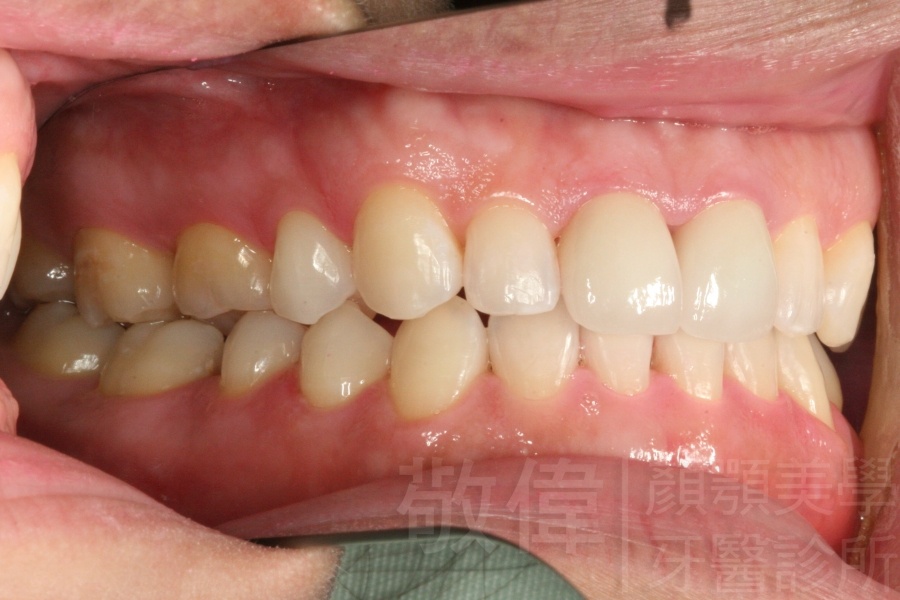

經由本院3D數影X光影像儀分析、與3D齒顎顏矯正技術,再配合口腔顎面正顎專科醫師施以正顎手術治療,雙方共同合作,使患者臉部外觀有很好的改善,大歪變小歪,產生了天南地北的大改變,她的人生也整個變得不一樣。

因為矯正與正顎手術的配合,使「戽斗妹」變成了「陽光正妹」,完全的改變了她的人生,在面對各種場合、與人交際都散發出自信微笑。所以,奉勸家長,如果小朋友有臉顎畸型的問題,應該考慮配合做這種簡單、安全、有效的正顎手術。

「3D齒顎顏矯正」,不止矯正您的牙齒,也會改變您的人生。「治療前」和「治療後」出社會的人生際遇一定會截然不同。